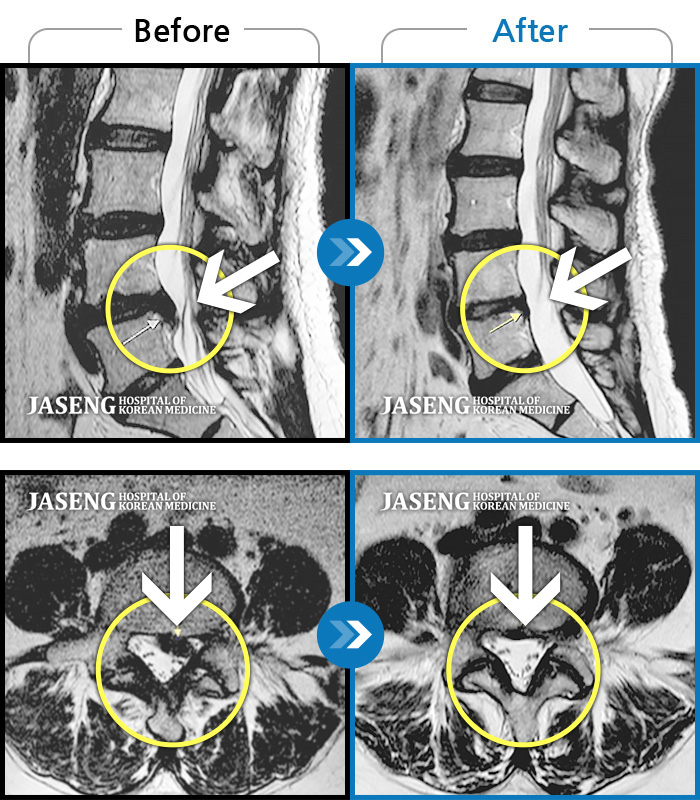

안녕하세요.방금 배아프다고 선생님찾아뵙고 진료받았죠 ㅎㅎ 후기를 이제서야 올리네요. 4년전인가 퇴행성디스크를 진단받고 양방병원 이곳저곳을 전전긍긍하며 속썩었던기억이나네요. 여러병원에서 수술을해야한다는 말에 젊은나이에 걱정을많이했었습나다. 심하게 아플때는 아침에 잠에서깨고 바로일어나지도못하고앉지도못해 회사생활이 힘들었는데 성생님만나뵙고 꾸준한치료 덕에 이렇게 허리가 안아프게되어 너무행복합니다. MRI는다른곳에서 찍어본거긴하지만 돌출된 디스크가 들어갔다는말에 신기했었습니다. 생활습관을바꾸고자 노력했고, 무엇 보다 선생님을 믿고 의지한 결과가아닐까 생각됩니다. 너무 감사드리고 MRI사진은 공유해드려야하는데 자꾸까먹네요 ㅎ